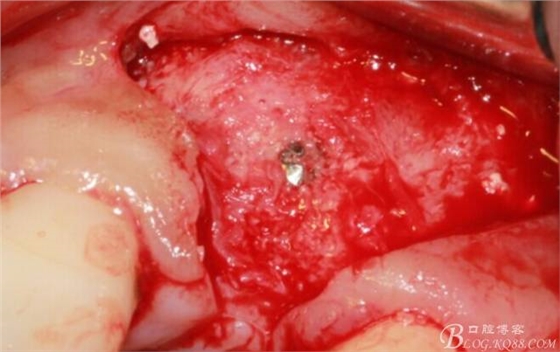

于是我果斷告知患者,手術(shù)失敗了,不能拖延,如不及時處理,炎癥繼續(xù)發(fā)展會很快波及鄰牙牙槽骨。患者接受我的建議。切開翻瓣,骨粉及生物膜消失了,骨吸收嚴(yán)重,幸運的是,因為處理及時,鄰牙骨支持依然存在。

徹底掻刮。

有老師問我,為什么不在此時同期植骨同期植入植體?我的觀點是:不要一次做太多事情,做得越多風(fēng)險越高。再說,此時軟組織不健康,沒有健康的軟組織如何能保證GBR的成功?所以,我僅放了一塊膠原蛋白就縫上了。